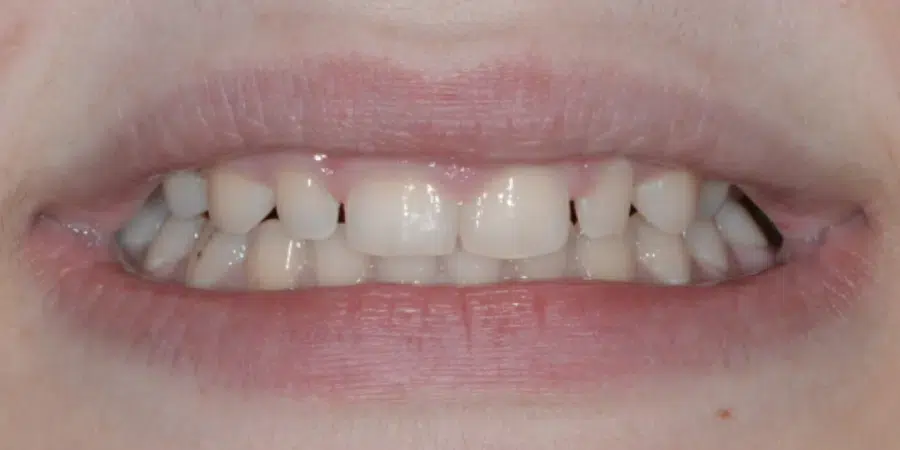

Caz de estetică dentară de fațetate directă la microscop

Provocarea acestui caz a constat în dorința expres a pacientei de a-și reconstrui dintiii prin tehnica de adiție cu materiale, fără prepararea lor. Am optat pentru tehnica minim invazivă de fatetare la microscop, folosind cele mai bune materiale de compozit cu particule nanoceramice.

Această tehnică se pretează doar pentru dinții mici, care pot căpăta volum, pentru dinții cu spațieri sau pentru dinții care tocmai au încheiat tratamentul ortodontic.

Timp de realizare 8h.